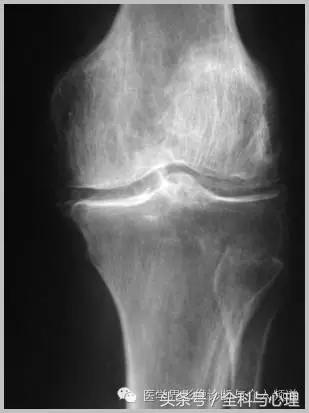

半月板钙化